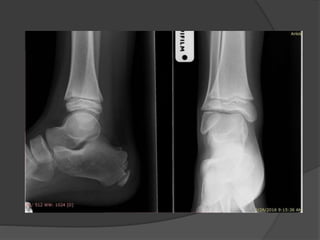

Case 1: A“healthy” 50 year old

Fell off a 3 ft high parapet

c/o pain, inability to bear weight on the right

foot

Initial radiographs

6 weeks later the cast was taken off, unable to bear

weight

Diagnosis

?

Lisfranc fracture- dislocation

Bony or ligamentous injury involving the tarsometatarsal

joint complex